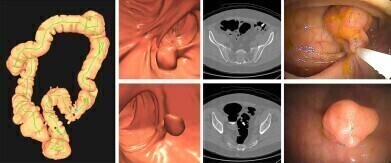

Images of positive CT colonography (CTC) screening examination result in an asymptomatic 67-year-old man. Credit: Radiological Society of North America

Dr. Perry emphasised that recent Medicare coverage expansions have improved access to less invasive modalities, including mt-sDNA testing – which analyses stool for cancer-specific biomarkers – and CT colonography, which employs imaging technology to render non-invasive visualisation of the colon polyps and tumours.